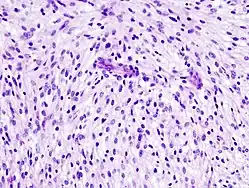

Badanie histopatologiczne

Badanie histopatologiczne materiału uzyskanego w biopsji lub preparatu pooperacyjnego umożliwia ostateczne rozpoznanie mięśniakomięsaka gładkokomórkowego, pozwala ocenić zaawansowanie choroby oraz dostarcza istotnych rokowniczo informacji. Rozpoznanie opiera się na ocenie atypii, martwicy i aktywności mitotycznej[30].

Nie ma specyficznego profilu immunohistochemicznego charakterystycznego dla mięśniakomięsaka gładkokomórkowego[30]. W większości przypadków tego nowotworu stwierdza się pozytywną reakcję w kierunku SMA, desminy i h-caldesmonu. Reakcja może być również dodatnia w przypadku keratyny, EMA, CD34 i S100. Reakcja w kierunku KIT (CD117), w odróżnieniu od guzów stromalnych (GIST), jest negatywna[31]. Nie rozpoznano typowych zmian w badaniach cytogenetycznych, często stwierdza się utratę regionów 3p21-23, 8p21, 13q12-13, 13q32 i uzyskanie dodatkowej kopii regionu 1q21-31[32].